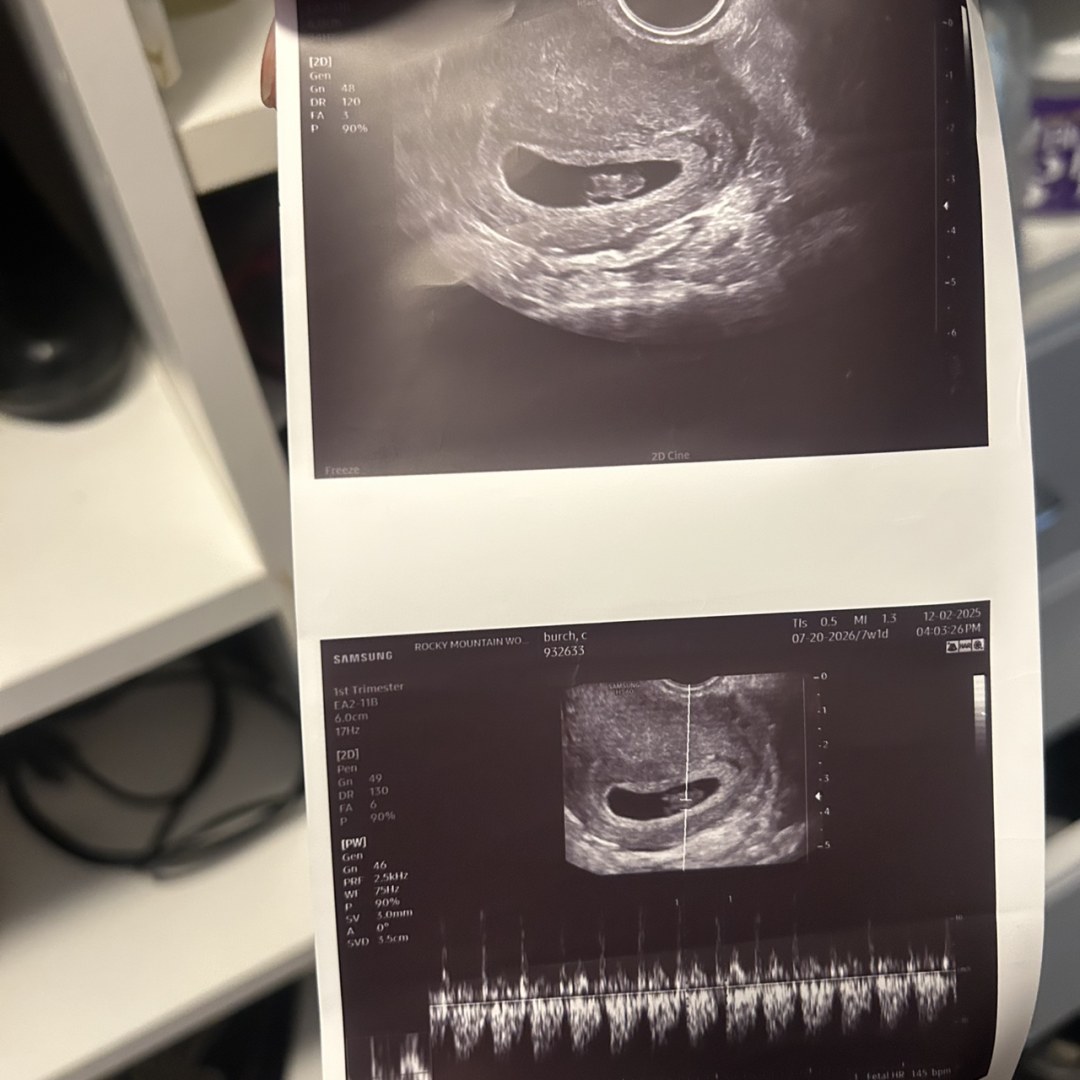

Elachye & Quariy Burch-Foster

Denver, CO

July 20, 2026

Welcome to our registry! We are so grateful for your love and support during this exciting time. We can't wait for you to meet our little one! These are some of the items we think we’ll need as our family grows. Your love means the world to us!💜💜